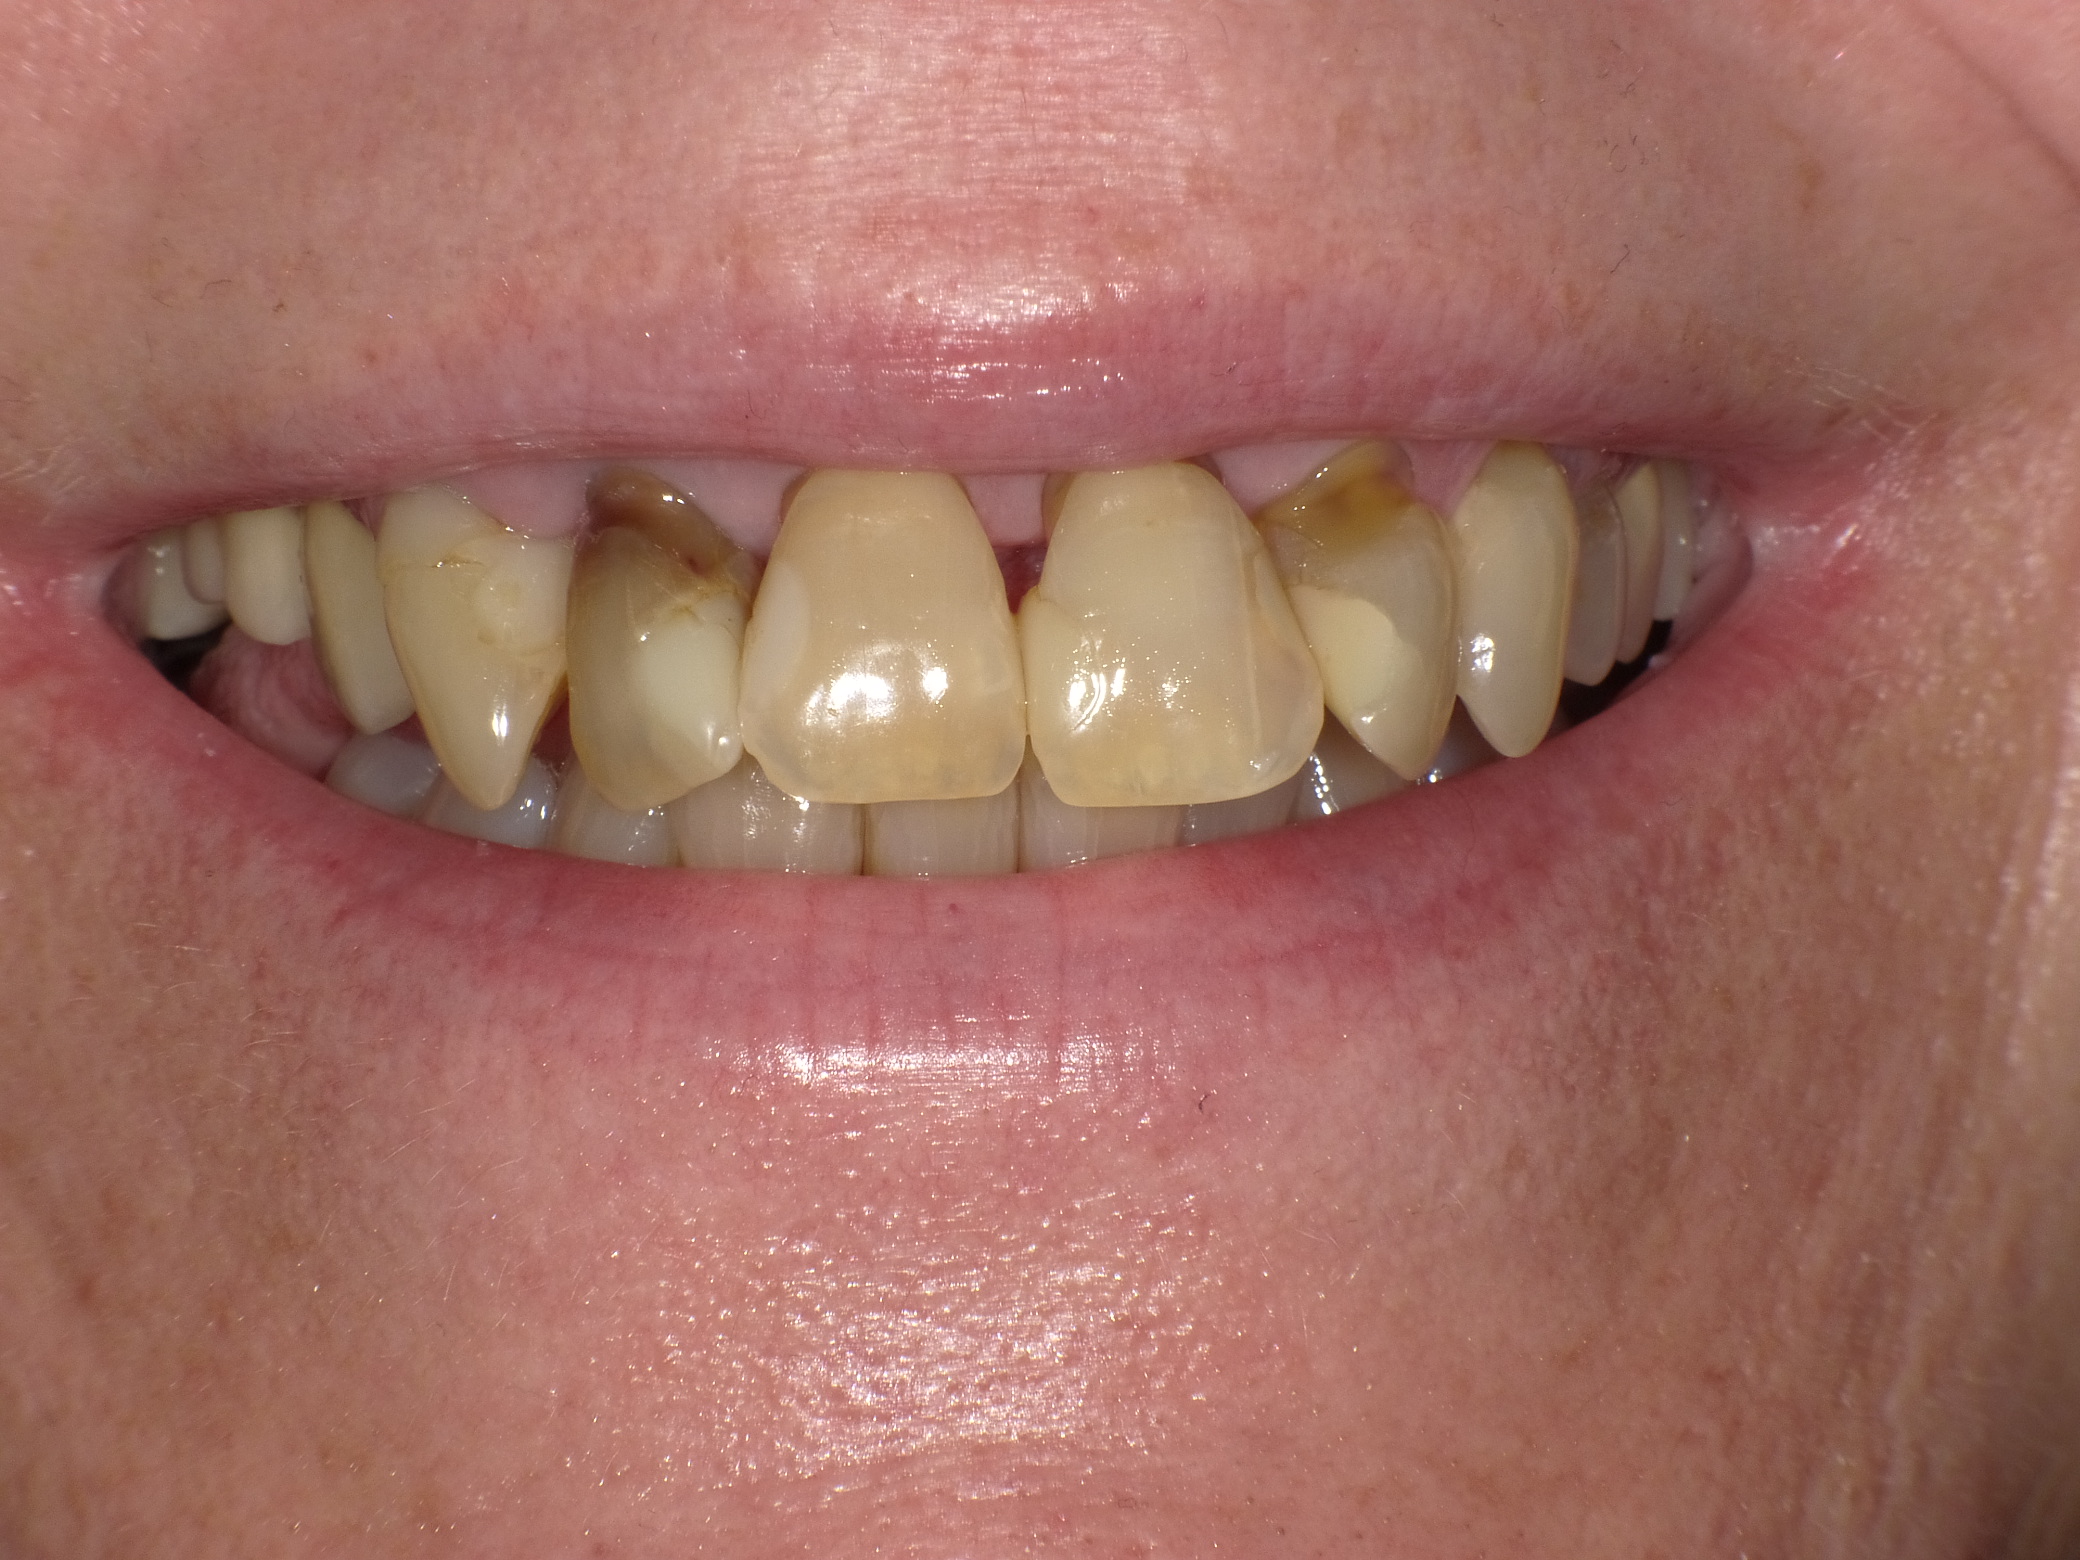

Abradierte, gelbliche Zähne mit vielen Kunststoff-Füllungen und Kronen, die der Patientin nicht gefallen haben

Vorher: Abradierte, gelbliche Zähne mit vielen Kunststoff-Füllungen und Kronen, die der Patientin nicht gefallen haben

Leuchtende Zähne durch vollkeramische Veneers und Teilkronen in nur 2 Terminen

Nachher: Leuchtende Zähne durch vollkeramische Veneers und Teilkronen in nur 2 Terminen